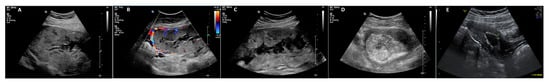

All patients with PAS presenting at our center between 2005 and 2021 were included. The outcome of 19 patients has already been published, focusing on physical, mental, and reproductive sequelae after the treatment of PAS [31,34]. Antenatal diagnosis of PAS was made using 2D ultrasound, color Doppler, and transvaginal ultrasound [35,36]. Ultrasound criteria included loss of the clear zone or decidua, partial or complete absence of the myometrium layer, sub-placental lacunae, a sudden break-off in the outline of the calcifications characteristic for third-trimester placental basal plates, increased vascular perfusion between the uteroplacental interface reaching the uterine serosa, bladder wall interruption, placental bulge, and exophytic mass hypervascularity (Figure 1) [8,35,36,37,38].

Figure 1.

(A–C) PAS in 34 + 0 weeks of gestation with loss of decidua, bladder wall interruption, placental bulge, and exophytic mass hypervascularity. (D,E) Placenta in situ on day 13 after CS with persistent bladder wall interruption. (F) Placenta in situ on day 63 after CS with a diameter of about 3.5 cm, well separated from the uterine wall, without perfusion. (G) Day 122 after CS; fluid-filled uterine cavity surrounded by a hyperechogenic rim.